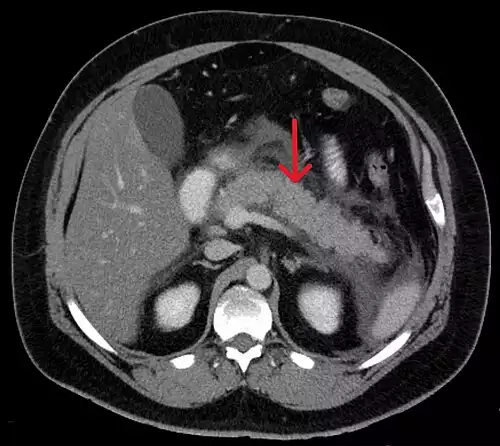

پانکراتِیت یعنی التهاب لوزالمعده ( پانکراس ). پانکراتِیت یا به صورت حاد بروز می کند یا مزمن.

گاهی اسکن رادیوایزوتوپ، رادیوگرافی شکم، سی تی اسکن یا سونوگرافی لوزالمعده و آندوسکوپی مفید می باشد.